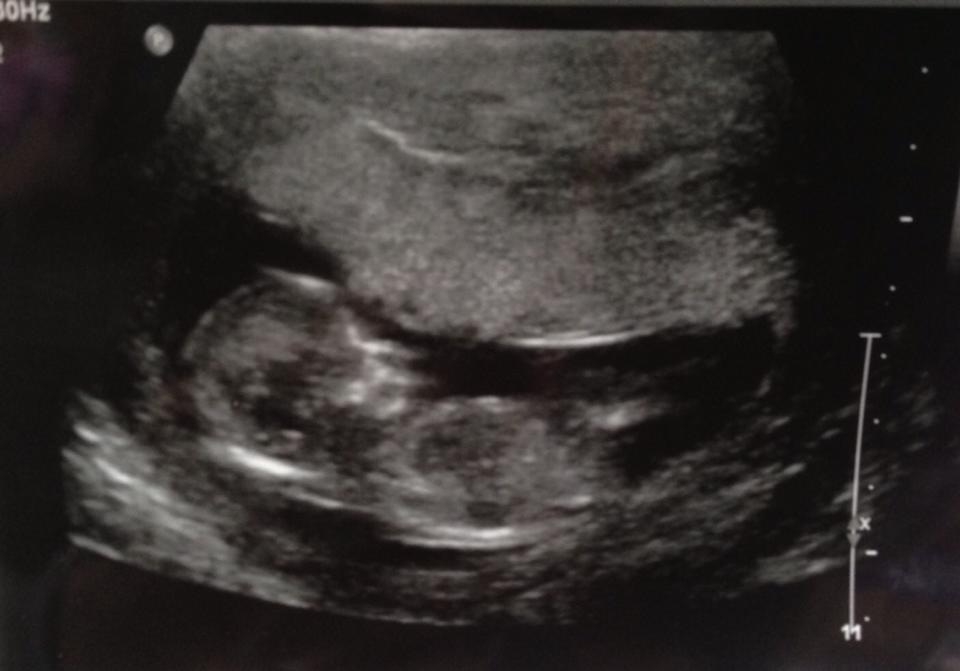

Hello. This ultrasound was taken at 12 week 2 days. Any guesses on a BOY or GIRL?!? Thank you. We find out next week on Valentine's Day! ❤Attachment 8681

Sorry I dont see nub on this pic :( x

maybe girl.